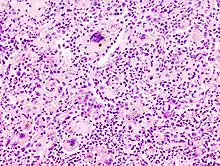

• Käsige Nekrose - Bsp.: Tbc (Epitheloidzelliges Granulom mit Langhans-Riesenzellen und zentraler käsiger Nekrose)

• Spezifische Entzündung - Entzündungsmanifestationen, die für eine Erkrankung typisch sind z.B. Tbc, Sarkoidose

LANGHANS-Riesenzellen in einem Tbc-Granulom, transbronchiale Biopsie